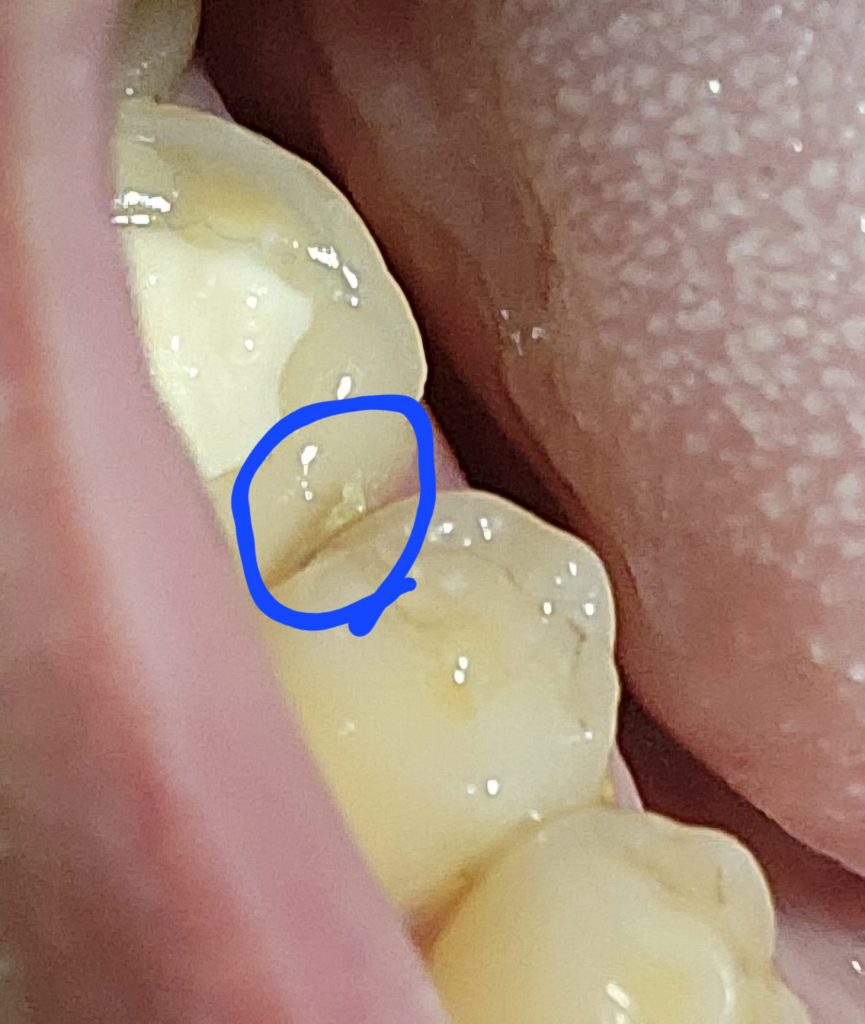

크라운 치료 중에 이빨과 이빨사이에 가시같은 이가 있습니다.

크라운치료 세번째갓다왓습니다 충전과정까지하고 다음에 본뜬다고 하더라구요 근데 크라운하려는이 잇몸에 가시같이 이가 있더라구요 건들이면 이리저리 움직이고 아픈데 나중에 제거하고 크라운 씌우려나요?

• 1번 째 사진

치과용 재료가 남은 것이거나 음식물 찌꺼기로 보입니다. 치실로 잘 제거 해보시기 바라며 잘 빠지지 않는다면 억지로 빼려고 하지 말고 치과가서 빼달라고 하면 됩니다.

본뜨기 전에 크라운 축면을 매끈하게 다듬는 과정에서 가시같다고 표현하신 부분은 정리해주실 겁니다.